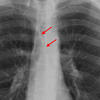

AzyEsop interf

Ex 1 arrows